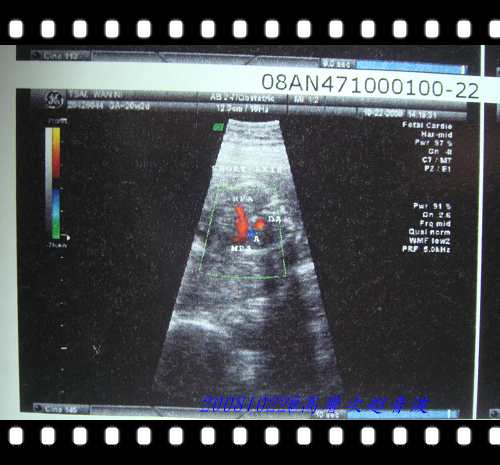

這張是照心臟的血液流向,藍色是舒張壓紅色是收縮壓

醫生說流向都正確,當然也有看心臟的發展狀況都是正常的....安心不少!!